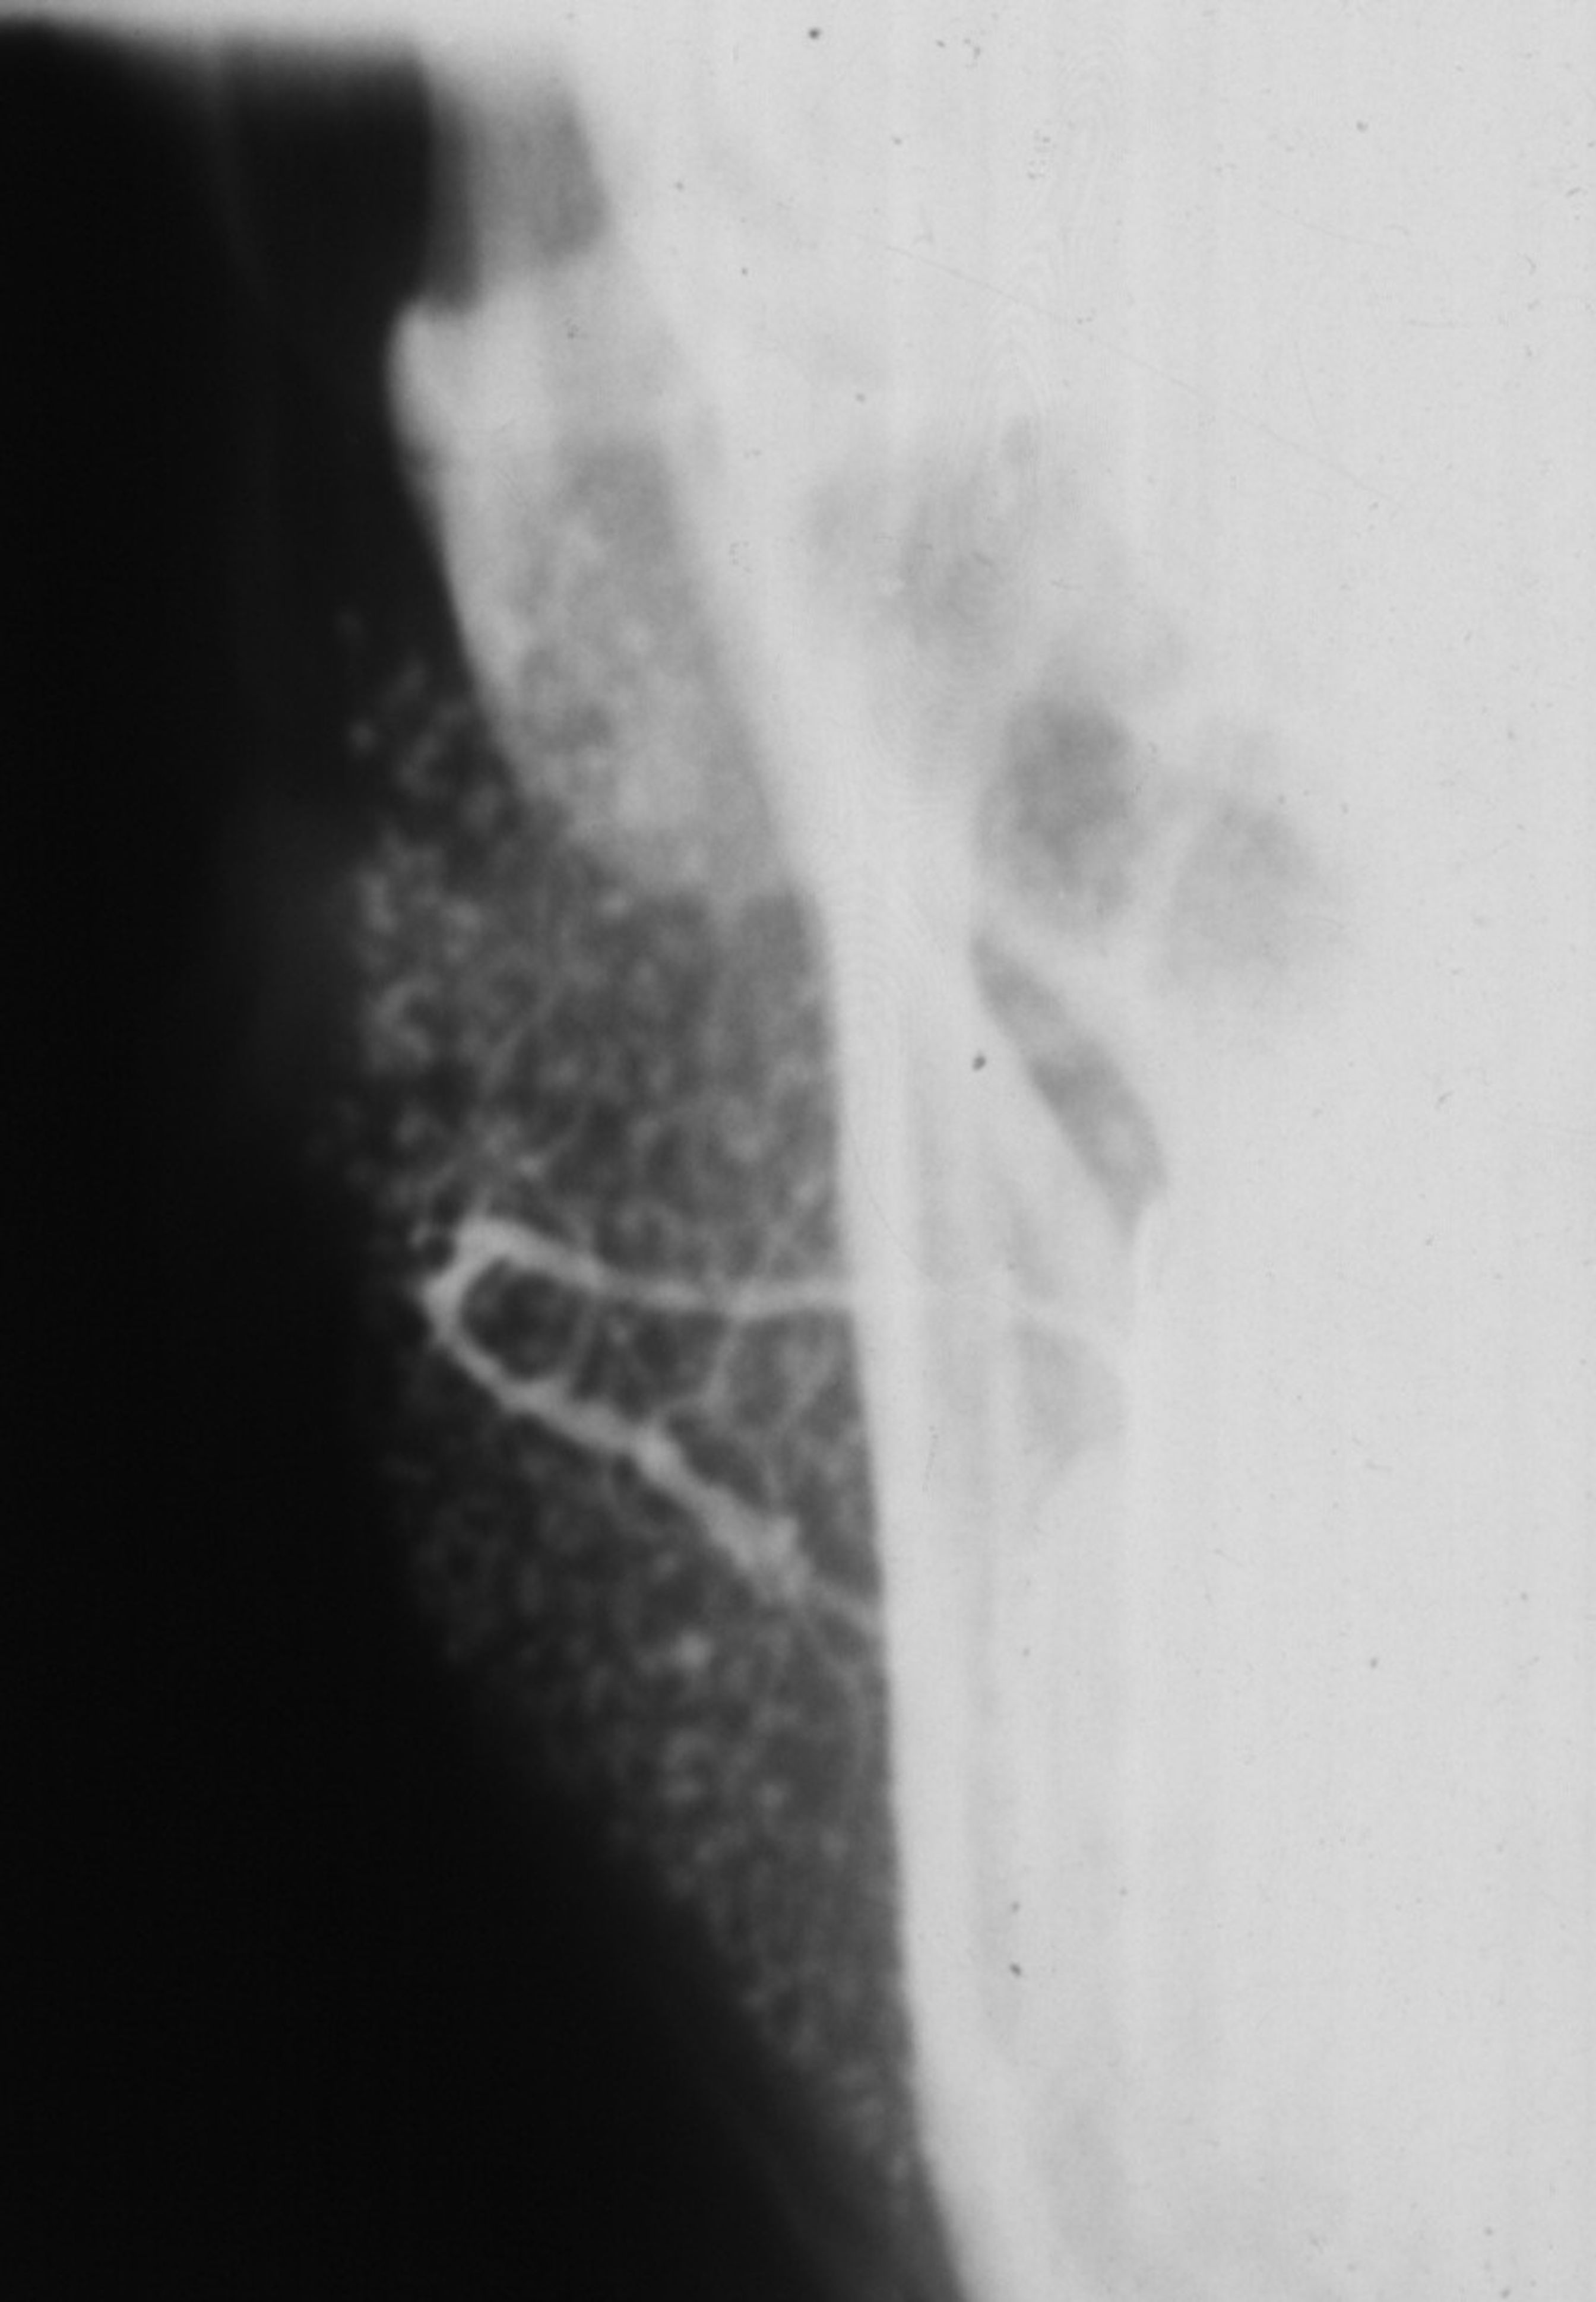

Imaging analyses, including ultrasonography and sialography, of the parotid glands were performed. Ultrasonographic features of the cervical region did not show any alterations of the submandibular and left parotid glands (Figure 2 through Figure 5). However, the right parotid gland demonstrated an inhomogeneous structure of the gland with scattered, multiple, small, oval, hypoechoic, or anechoic areas, usually well defined, and increased parenchymal blood flow. Sialographic examination of the right parotid gland showed a snowflake-like form and Christmas-tree pattern and evidence of sialoangiectasia without any changes of duct anatomy (Figure 6). Even after the salivary stimulation, the duct system was kept filled by the contrast fluid that again highlighted the sialectatic changes (Figure 7).

Fig 6. Sialogram showing a Christmas-tree pattern and uniform shape of the right parotid gland.

Table 6

Fig 7. Sialogram showing the presence of sialectasia of the right parotid gland after the salivary stimulation.

Figure 7